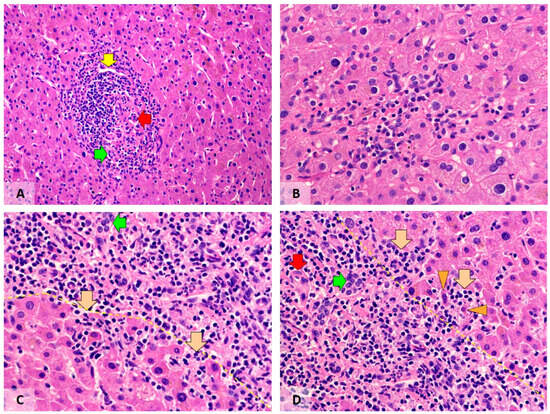

Morphological and Immunohistochemical Characteristics of Liver Inflammation in Patients with a History of COVID-19

The COVID-19 pandemic caused more than seven million deaths, mostly via acute respiratory distress syndrome with microvascular thrombosis. Compared to the amount of information about pulmonary pathology, information about COVID-19-induced liver lesions is scarce, especially with regard to the long-term consequences. The aim of our study was to evaluate inflammatory, vascular and fibrotic changes in hepatobiliary tissues of patients with a history of COVID-19 (post-COVID-19 patients). Based on the Knodell score, moderate portal inflammation was observed in 41.2% of post-COVID-19 patients, contrasting with 14.3% of control cases (p = 0.06). Moderate periportal inflammation was present in 26.5% and 7.1% of patients, respectively (p = 0.08). Post-COVID-19 patients showed higher counts of CD3+ lymphocytes (p = 0.02) and lower counts of CD68+ macrophages (p = 0.04), as well as more frequent and extensive regenerative changes in hepatocytes and the biliary epithelium (p = 0.0007). We did not find significant fibrosis or pathological changes in blood vessels, and only mild steatosis was observed in both groups.